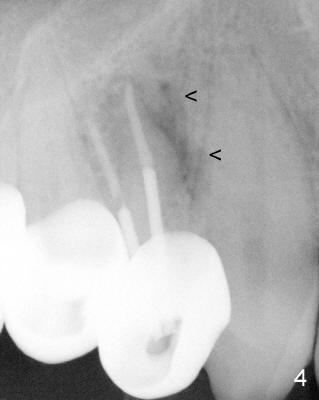

A 68-year-old male patient presented to office in March 2011 with chief complaint "upper right tooth is not comfortable". Clinical exam shows missing teeth: #13,14,30, and 31, replaced by removable partial dentures. The tooth #5 has mild mobility and percussion. Pocket depth is within normal limit. X-ray shows no significant finding (Fig.1,2). Three months later, he returned with chief complaint "The tooth has swelling". It appears that there is exostosis on buccal aspect of upper teeth. There is no erythema or tenderness on buccal mucosa around the tooth #5). But X-ray shows periradicular radiolucency (arrowheads in Fig.3,4). Cone Beam CT was recommended to confirm diagnosis of root fracture. Approximately one month later, abscess developed with fistula formation. Symptoms were controlled by taking Amoxicillin. On August 2, 2011, the patient returned for prophylaxis. The fistula was present (arrowhead in Fig.5). Gutta percha #30 was inserted into the fistula. PA was taken. The point of the gutta percha (blue arrowhead in Fig.6) points to enlarged periradicular radiolucency (black arrowheads). Deep pockets were in distobuccal and lingual. Decision was made to extract the tooth. Fig.7 shows the socket immediately extraction. The buccal plate is perforated. The septum (*) is not intact. Cracking sounds were heard during extraction. In fact the lingual root is obliquely fractured with exposed post (Fig.8: *). There is another cracking line from the buccal root to the lingual one (arrowhead). In brief, the earliest sign of root fracture is nonspecific. It should alert us to its suspicion.